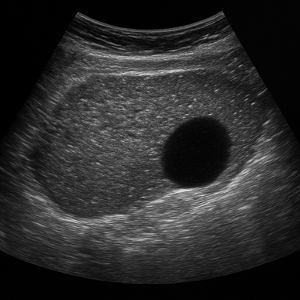

신장과 부신

신장은 결석, 수신증(소변이 막혀 고여서 생긴 변화), 낭종, 종양 등의 상태를 초음파로 볼 수 있어요. 부신은 위치가 작고 깊지만, 우연종 같은 병변이 의심될 때 관찰할 수 있답니다.

신장 결석, 신부전, 낭종

- 신장 결석

콩팥에 생긴 작은 돌들은 초음파에서 반짝이며 그림자를 동반해 쉽게 보일 수 있어요. - 신부전 (수신증 등)

소변이 막혀서 신장이 붓는 상태를 ‘수신증’이라고 하는데요, 초음파로 신장의 부종이나 이상을 확인할 수 있어요. - 신장 낭종이나 종양

주머니처럼 생긴 낭종이나 덩어리가 있으면 초음파로 확인 가능해요.

혈뇨

소변에 피가 섞여 나오면 신장이나 요로에 문제가 있을 수 있어요. 혈뇨의 원인이 될 수 있는 신장 결석, 낭종, 종양, 수신증(소변이 막혀 신장이 부어오르는 상태) 등을 복부초음파로 확인할 수 있어요.